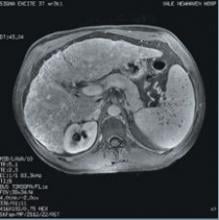

Cedara Software today announced that it will unveil several new oncology solutions, including multimodality image fusion that supports deformable registration in PET/CT software, at the American Society of Therapeutic Radiology and Oncology Conference (ASTRO), held November 5-9 in Philadelphia, Pennsylvania.